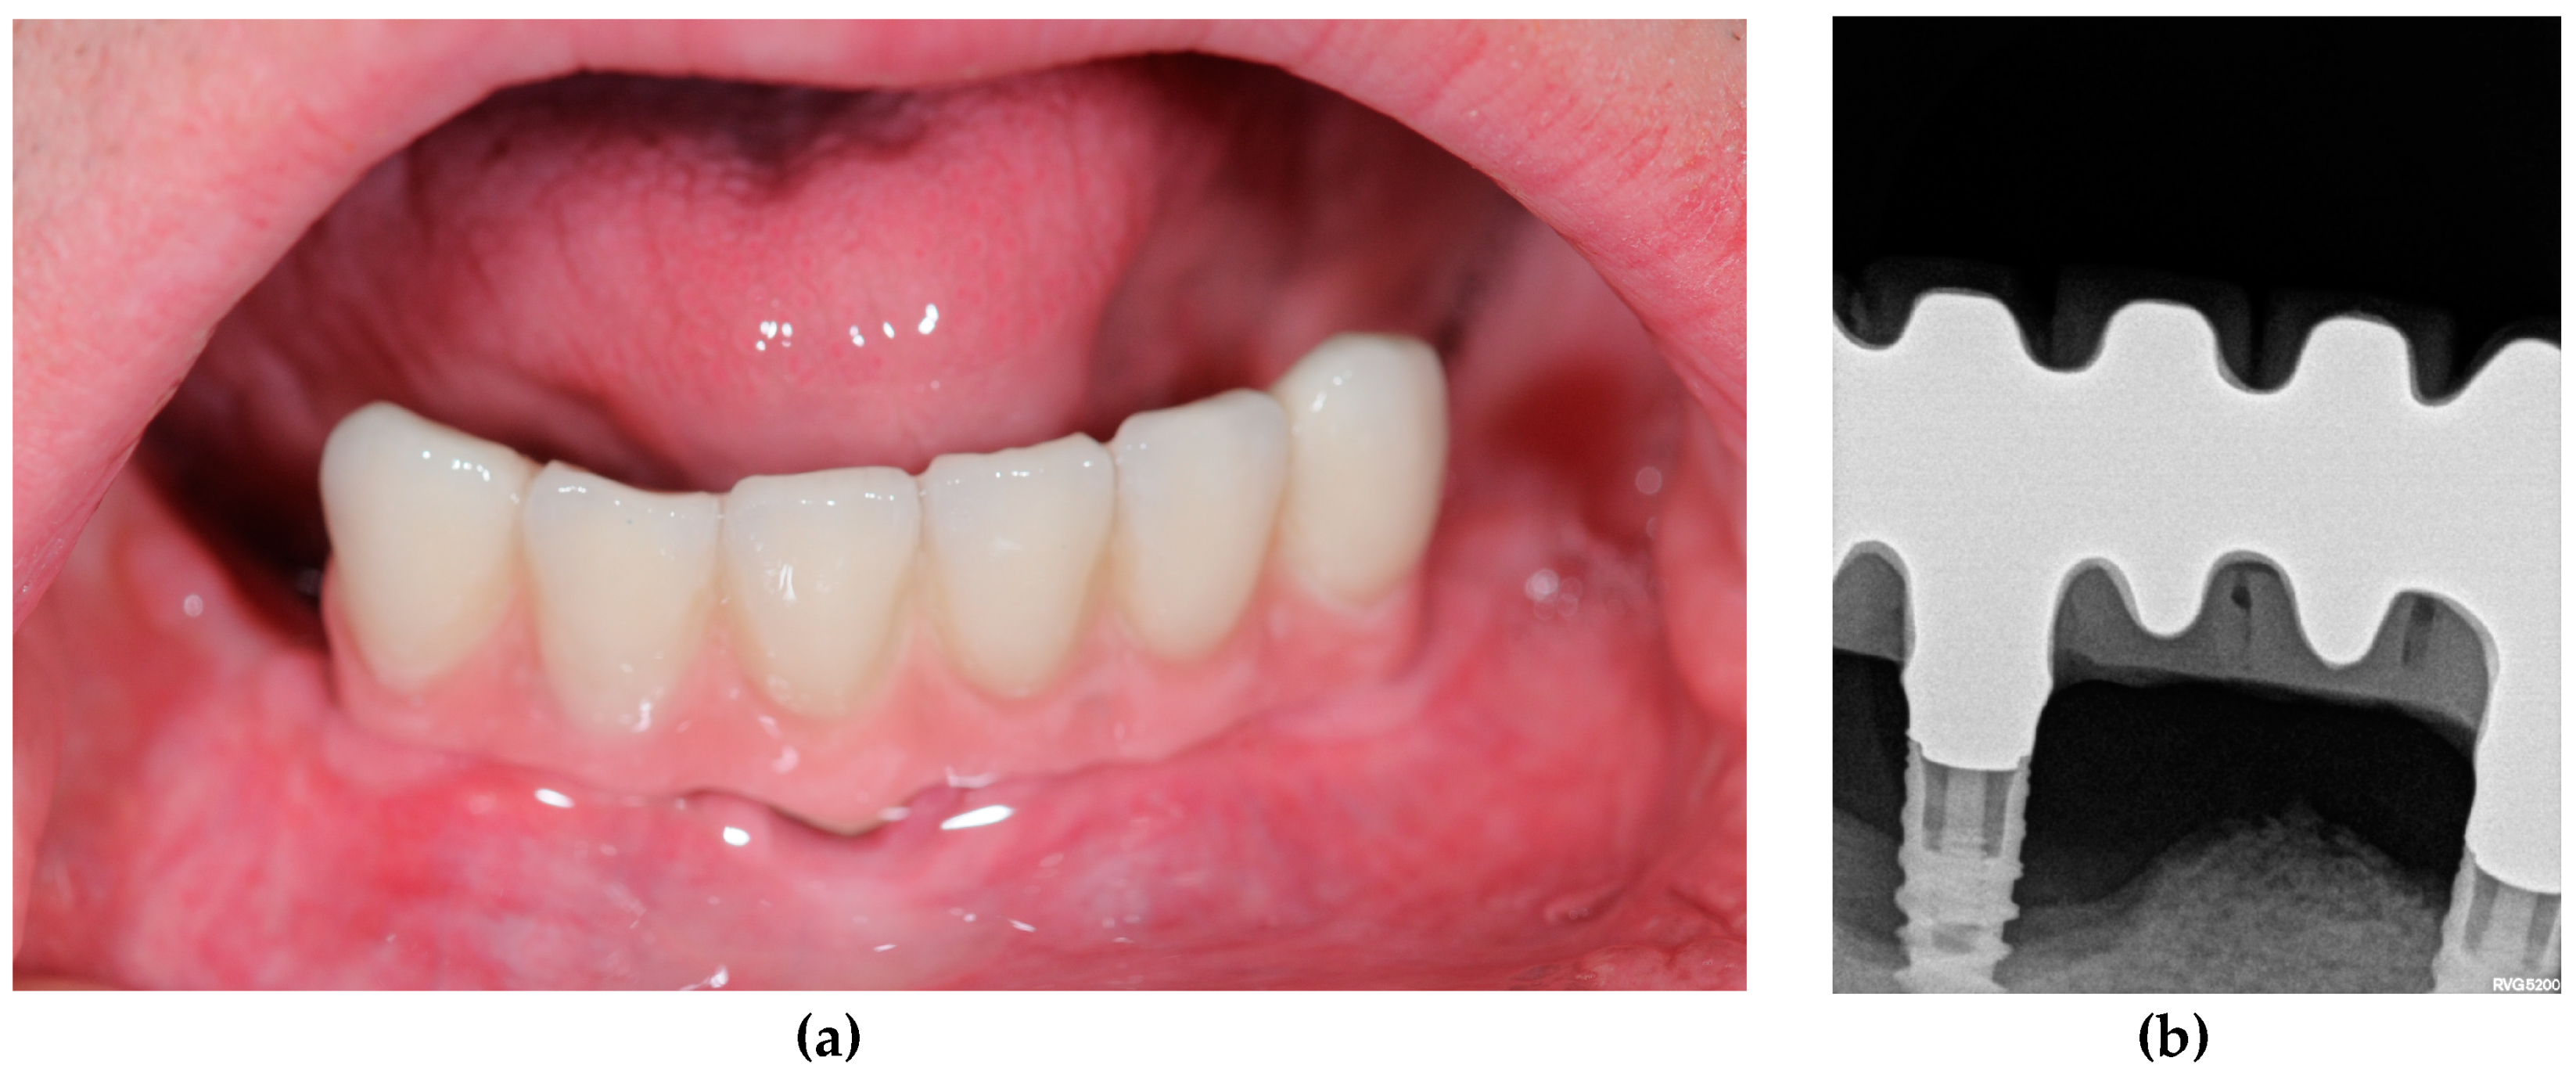

- Down syndrome patients who have suffered aggressive periodontitis and for whom implant treatment has failed.

- Down syndrome patients who have not suffered aggressive periodontitis and have a positive experience of implant treatment (more than two years’ follow-up without bone loss problems (grade 1 on the Lavergall and Jansson scale) [14].

| 1 | +PD+FI | 41 | Female | No | No | Yes | 2 implants | No | 1 implant lost and 1 implants with severe peri-implantitis |

| 2 | +PD+FI | 39 | Female | No | No | Yes | 3 implants | No | 1 implant lost and 2 implants with severe peri-implantitis |

| 3 | +PD+FI | 33 | Male | No | No | Yes | 4 implants | No | 2 implants with severe peri-implantitis |

| 4 | +PD+FI | 35 | Male | No | No | Yes | 12 implants | No | 3 implants lost |

| 5 | -PD-FI | 40 | Female | No | No | No | 3 implants | No | No implant failure or peri-implantitis |

| 6 | -PD-FI | 34 | Female | No | No | No | 2 implants | No | No implant failure or peri-implantitis |

| 7 | -PD-FI | 43 | Female | No | No | No | 3 implants | No | No implant failure or peri-implantitis |

| 8 | -PD-FI | 48 | Female | No | No | No | 2 implants | No | No implant failure or peri-implantitis |